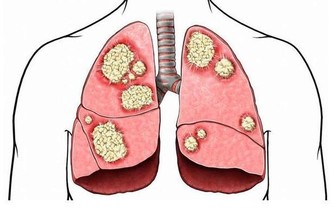

如果你睡眠很好、堅持鍛煉、吃得健康,並且壓力有限,但仍然總是很累,那麼最好去看看醫生。

因為下列疾病可以導致過度疲勞:貧血、焦慮症、慢性疲勞綜合症、抑鬱、糖尿病、食物不耐受、心髒病、營養素缺乏症、甲狀腺功能減退症、懷孕、尿路感染等。